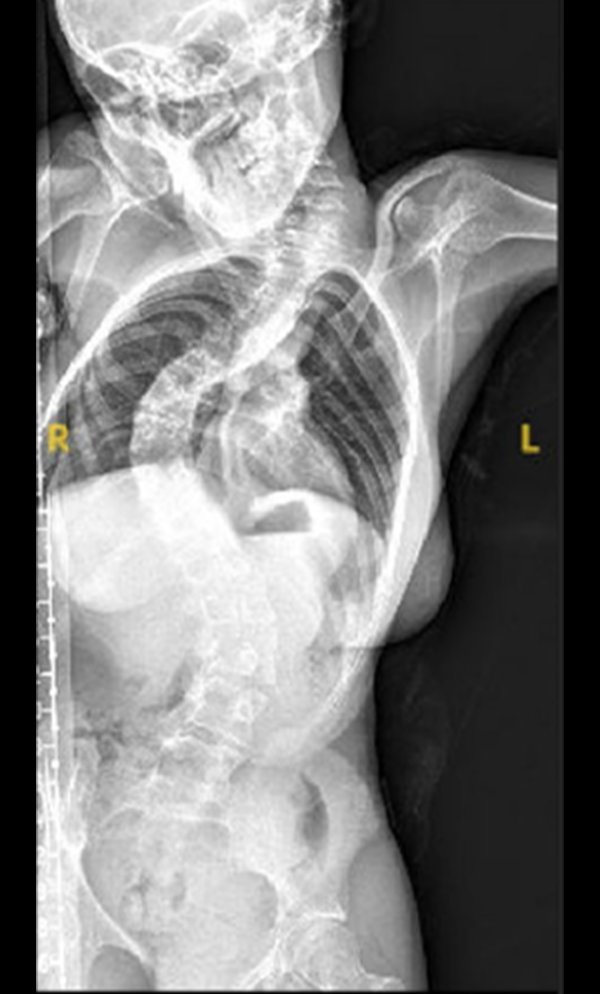

Scoliosis is a common condition characterized by a sideways curvature of the spine, often emerging during puberty. While its origins can vary, most cases are mild. However, without proper attention, severe deformities may lead to significant functional disabilities, impacting lung function and overall well-being.

Gallery : Before - After

After

Before